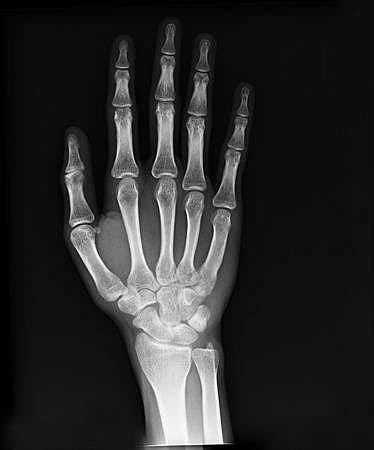

• Imagen de mano

Imagen de mano

Rontgen obtuvo la imagen de la mano de su esposa. Consiguió este resultado al poner una placa fotografía detrás de la pantalla.